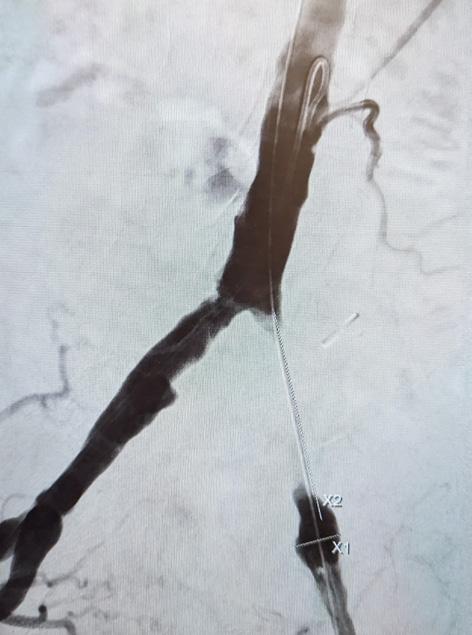

Particularly interventions that require a large dissection or insertion of synthetic grafts benefit from a hybrid approach. Bypass surgery, where the proximal intervention’s patency is dependent on the distal runoff or iliac PTA and common femoral endarterectomy with or without bypass, should be performed either simultaneously or soon thereafter to prevent thrombosis of the proximally treated artery or the bypass graft. Many centers have implemented the practice of completion angiography for all peripheral bypass surgeries to verify the patency of the inflow, outflow and the graft to prevent early occlusions of the graft. Upon identification of a technical defect immediate treatment can be performed by the operating physician at

the index procedure, such as revision of an anastomosis, excision of a retained valve or ballooning or stenting of a residual stenosis, dissection or tandem lesion.

Common femoral endarterectomy, combined with open iliac artery transluminal angioplasty and stent as well as Iinfrainguinal bypasses distal to either an iliac or superficial femoral artery (SFA) lesion are ideal candidates for a combined approach.